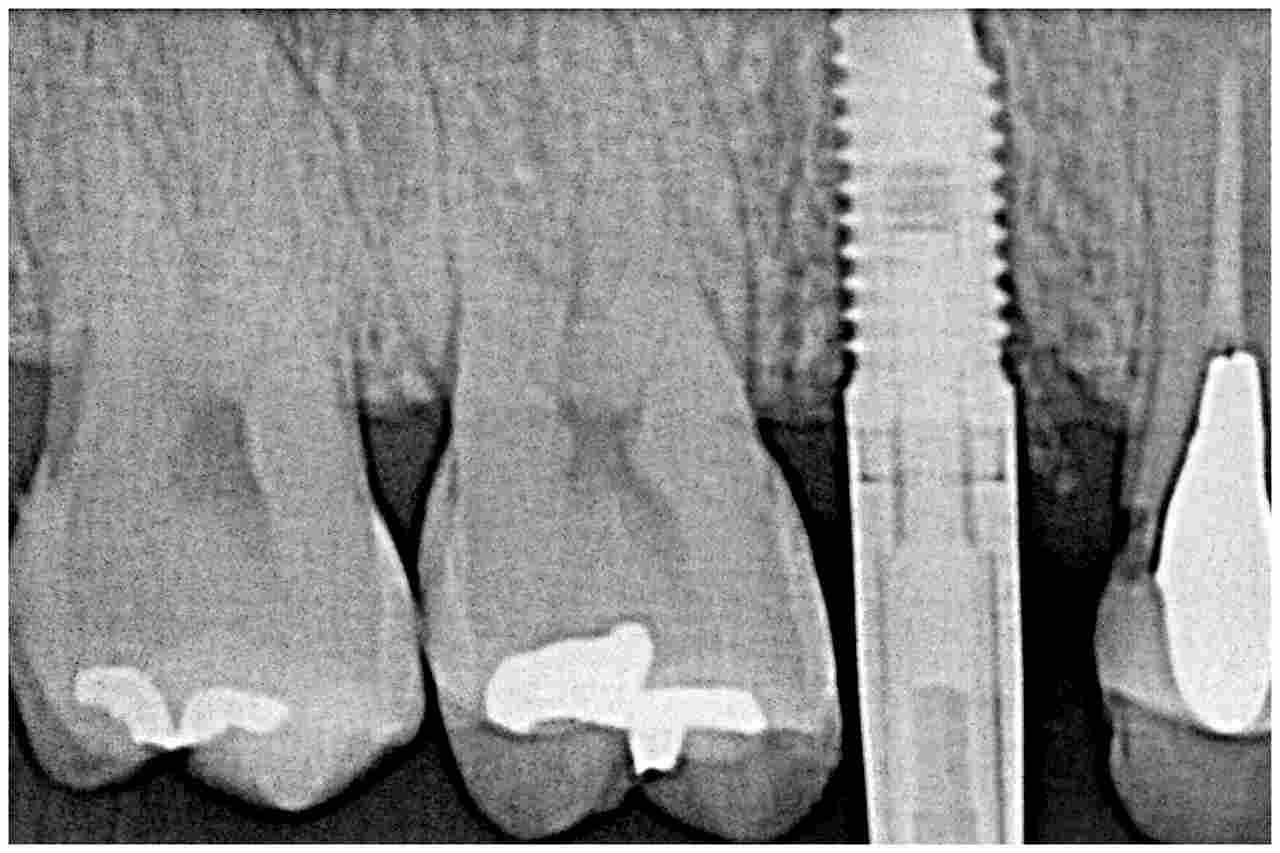

ブログ一覧|広島市安佐南区の歯科医院 ブログ一覧 トップ ブログ一覧 お知らせ スタッフブログ ブログ一覧 お知らせ 2021/10/20 右上の親知らずの難抜歯 上顎埋伏歯の抜歯 30代女性 お知らせ 2021/10/19 右上5番の上部構造の作成 インプラントにて機能回復を行っていきます お知らせ 2021/10/19 右上の歯が土台ごと取れた診てほしい ブリッジか? インプラント治療かで考える一面です お知らせ 2021/10/18 左上の6番の銀歯を外して白いセラミックへやり変えていきます セレックセラミックを用いた審美治療 お知らせ 2021/10/18 左下6番の銀歯をやり変えて白いセラミックへ 40代女性 お知らせ 2021/10/16 左下の親不知の難抜歯 40代男性 かなりの深い位置に親知らずが存在していました お知らせ 2021/10/16 右下親知らずの難抜歯 30代女性 親知らずが時たま痛くなる もう抜きたい お知らせ 2021/10/15 右上奥歯が急に何もしなくても酷く痛む 診てほしい 40代男性 << 1 2 3 4 5 … 233 234 235 236 237 … 870 871 872 873 874 >> Web診療予約 初めての方へ 選ばれ続ける理由 院内設備について 歯が痛いしみる一般歯科 歯がぐらぐらする歯周病 健康な歯を保ちたい予防歯科 子供の虫歯予防をしたい小児歯科 銀歯をセラミックに審美歯科 白い歯を目指しませんか?ホワイトニング 矯正専門医がいるので安心矯正歯科 抜けた歯を補いたいインプラント・入れ歯 医院案内 スタッフ紹介 メリィハウス歯科クリニックオフィシャルホームページ ラベンダー歯科クリニックオフィシャルホームページ お知らせ・ブログ ホーム 診療科目 一般歯科 歯周病治療 予防治療 小児歯科 審美治療 ホワイトニング 矯正歯科 入れ歯・インプラント マウスピース矯正 初めての方へ 院長・スタッフ 設備紹介 医院案内・アクセス メニューを閉じる